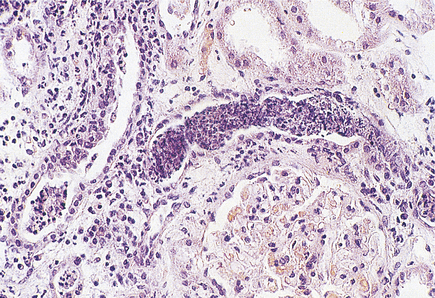

Histologically, the characteristic lesion is a focal and segmental glomerulonephritis. With increasing severity, segmental necrosis with fibrin deposition, and a florid crescentic glomerulonephritis occurs (Fig. 21.5).

image

Fig. 21.5 Anti-glomerular basement membrane disease. The glomerular injury in this case is due to anti-glomerular basement membrane antibody. image The resulting damage causes obliteration of the Bowman’s space by macrophages, inflammatory cells and epithelial cells forming a crescent. image Immunofluorescence reveals linear deposition of immunoglobulin on the glomerular basement membrane.